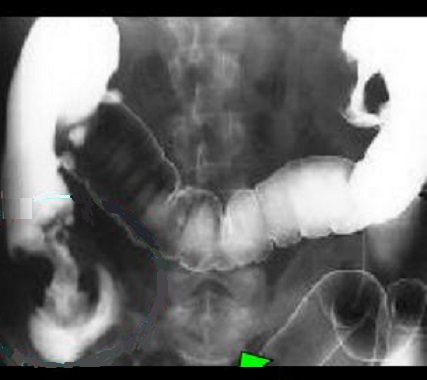

Image de

soustraction laculaire et stenosant d'une

adenocarcinoma du colon descendant sigmoidienne .

Lavemant baryte mono de contrast |

Image radiologique de lavement

baryte en mono de contrast avec aspect de soustraction

stenosant irreguliere d'une adenocarcinome du colon

sigmoide . La bord de la portion stenosant est tres

irregulie et durcissement . |